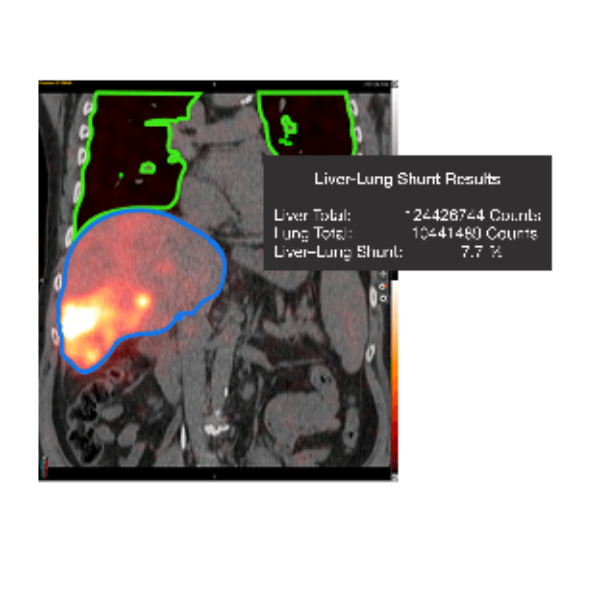

- Calculate liver-lung shunt fraction from both planar and SPECT images.